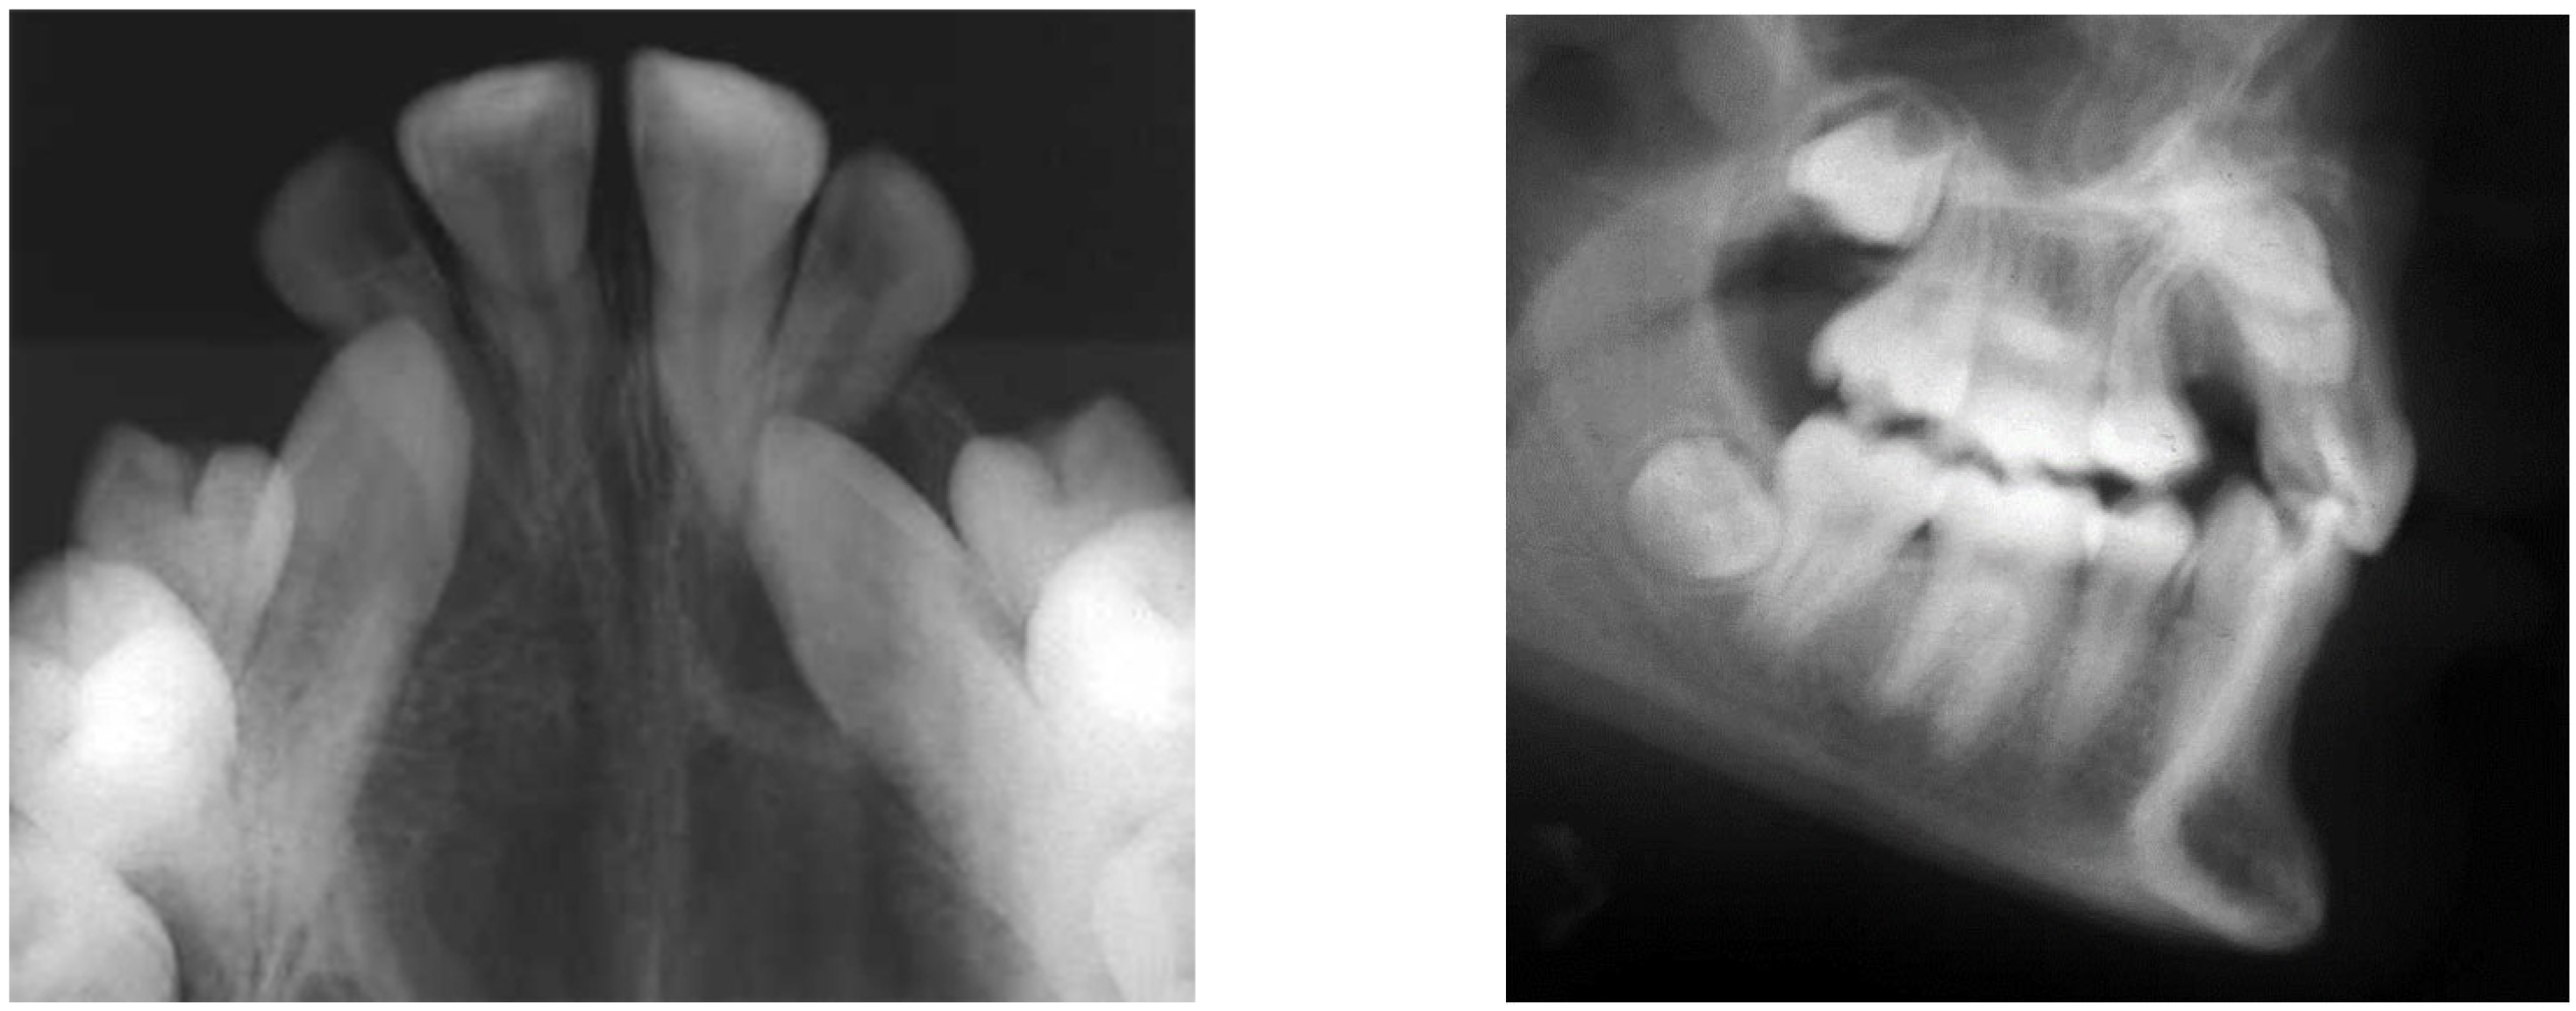

Two-Dimensional Radiographic Diagnosis of Maxillary Canine Impactions

2.2. Data Collection

2.3. Data Analysis